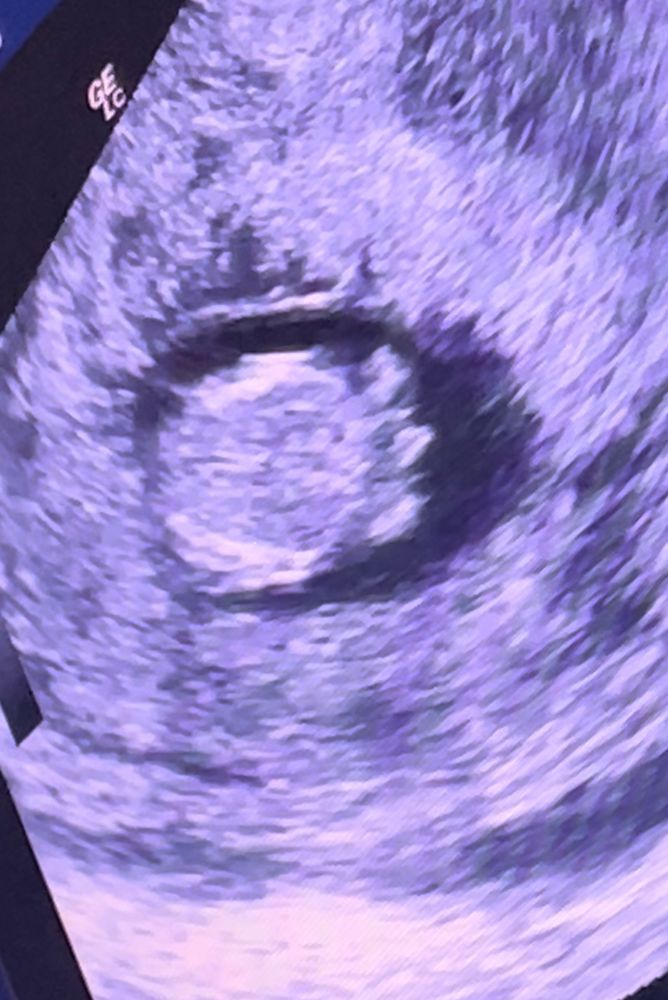

Вчера была на узи ,сказали что будет мальчик прям с ходу ,а я так надеялась на девочку 😄

сидела вчера и пересматривала видео с узи,я конечно увидела все прелести мальчика )) но надежда меня еще не покидает

Девочки посмотрите вы ,может у кого так тоже было и это все же пуповина ))))

жду ваше мнение 😄

Из девочки в мальчика еще может поменяться, а вот наоборот 🤔